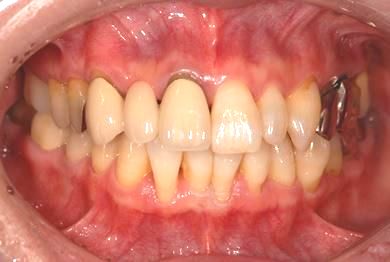

| 性別/年齢 | 女性 / 50歳 | ||||||||||||||||||||||||||||||||

| 主訴 | 銀のかぶせが取れたところと、痛みがある歯をセラミックで治療したい。 | ||||||||||||||||||||||||||||||||

| 治療内容 | メタルボンドセラミック3本(メタルボンドセラミッククラウン用土台3本) | ||||||||||||||||||||||||||||||||

| 総治療費 | 374,063円 | ||||||||||||||||||||||||||||||||

| 治療期間 | 10ヶ月 |